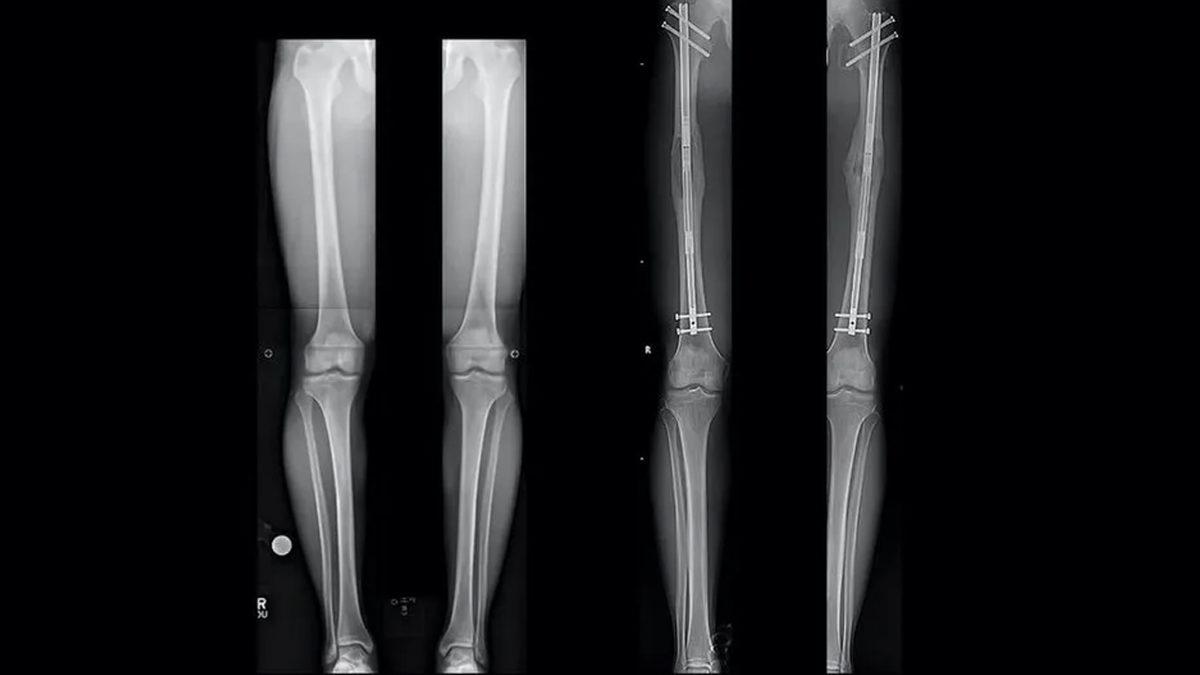

Boy uzatma ameliyatı, oldukça karmaşık ve dikkat gerektiren bir süreç. Ameliyat, genel anestezi altında, uzman bir ortopedik cerrah tarafından gerçekleştiriliyor. Prosedür, temelde iki ana aşamadan oluşuyor: osteotomi (kemik kesimi) ve distraksiyon osteogenezi (kemik uzatma).

Kesim yapıldıktan sonra ise kemik uzatma cihazının kemiklere yerleştirilmesi de distraksiyon osteogeneziyi ifade ediyor. Cihaz genellikle dışarıdan ayarlanabilen bir çerçeve veya içten ayarlanabilen bir çubuk oluyor.

Ameliyattan sonra bu cihazın ayarları düzenli olarak değiştirilerek, kesilen kemik aralığı yavaşça açılıyor. Süreç, yeni kemik dokusunun bu boşluğu doldurması için zaman tanıması için gerekli. Distraksiyon, günde birkaç milimetre olacak şekilde ayarlanıyor ve bu birkaç ay sürebiliyor.